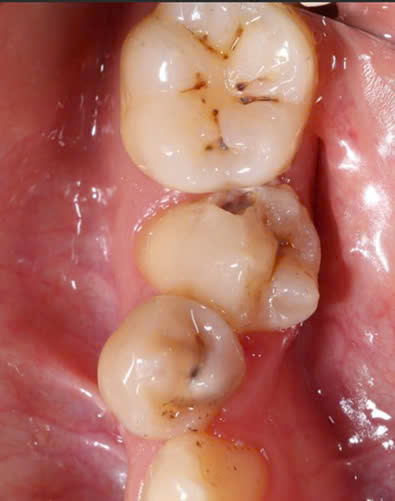

Hình 2: Sâu răng ở bệnh nhân mang thai

Phụ nữ mang thai thường ăn nhiều bữa nhỏ, tạo điều kiện cho axit tồn tại trong miệng gây sâu răng. Đặc biệt, trong thời gian ốm nghén, việc chải sạch răng hàm bên trong trở nên khó khăn hơn. Bên cạnh đó, thói quen ăn vặt để chống buồn nôn và việc vệ sinh răng miệng không đúng cách cũng làm tăng nguy cơ sâu răng. Môi trường pH trong miệng thay đổi và tính chất nước bọt bị biến đổi, tạo điều kiện thuận lợi cho vi khuẩn xâm nhập và tấn công răng lợi.